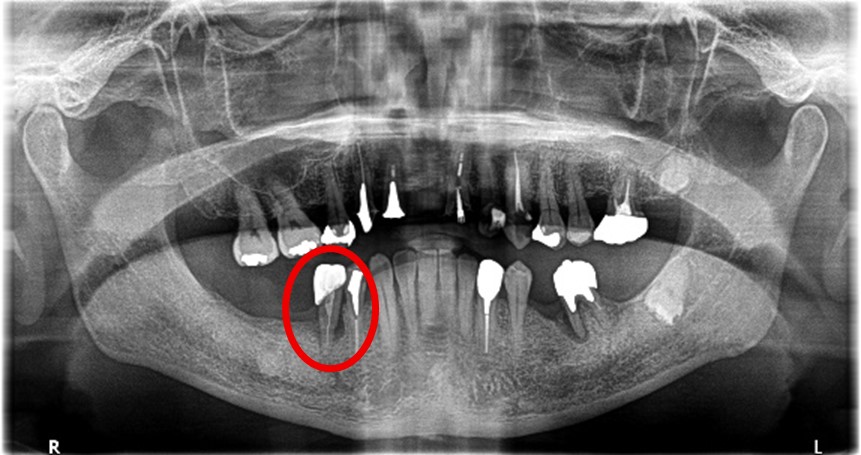

男性 Nさん 70代 (インプラント)

主訴

右下奥の歯が、グラグラして噛むと痛い。

治療内容

歯根の周りの骨が全く無い状態でしたので、保存することができず抜歯しました。3本歯がないところに2本インプラントを埋入しました。

所感

抜歯後、歯がなくなったところを補う方法には、部分入れ歯とインプラントがあります。この症例の場合、右下以外ほとんど歯が残っていますので、もし部分入れ歯にした場合、入れ歯のところで他のところと同じ感覚で噛むことができないので、慣れることが大変です。また部分入れ歯の支えになっている歯に負担がかかりますので、今後さらに歯を失う可能性が大きくなります。インプラントは、自分の歯と同じ感覚で噛むことができ、単独で植立していますので他の歯に負担がかかることがありませんので、更に歯を失うことを防ぎます。

インプラント2本:¥363,000×2本=¥726,000(税込)

ポンティック1本:¥115,500(税込)

合計:¥841,500(税込)

Before

※赤丸を抜歯しました。

After